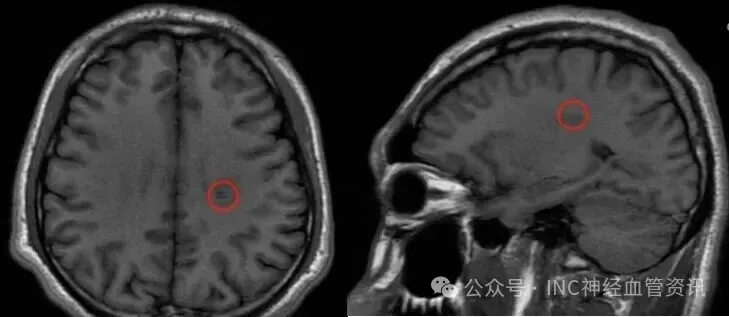

2022年5月,大学生斌斌突发右手沉重无力,持笔书写出现明显障碍。初期误认为复习疲劳,但数日后右腿开始乏力,行走时有踩棉感。随即进行的MRI检查结果显示:左侧半卵圆中心区存在8.0x11.0mm类圆形异常信号灶,诊断为海绵状血管瘤出血。

2023年3月术前MRI显示病灶体积较小,精准定位难度较大。2023年4月,通过INC中国代表处联系巴特朗菲教授进行远程咨询。教授评估认为:"通过中央前沟入路,结合神经导航和术中超声技术,可实现病灶精准切除,且不会造成新的运动功能障碍。"